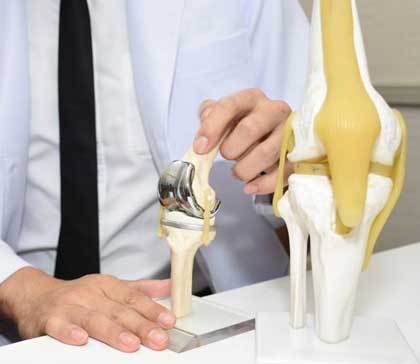

Knee replacement, also known as knee arthroplasty, is a surgical procedure to replace the weight-bearing surfaces of the knee joint to relieve pain and disability, most commonly offered when joint pain is not diminished by conservative sources and also for other knee diseases such as rheumatoid arthritis and psoriatic arthritis.